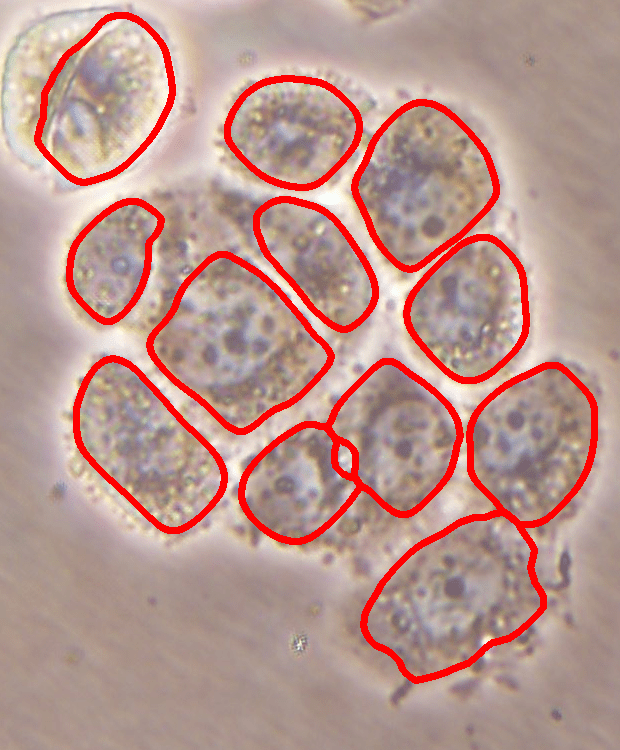

Automating the analysis of live cell morphology is critical for high throughput screening as this facilitates fast and reproducible measurements under inverted microscopy. The crucial step of this automation is to correctly identify cell morphology and distribution on culture plates. This requires detecting the cell locations whose difficulty lies along a wide range, from easy to very challenging, depending on visual characteristics of the cells. This step becomes difficult when cells appear in varying colors, brightness, and irregular shapes. The difficulty further increases when they grow in overlayers, and as a result, appear as cell clumps.

Before the advances in deep learning, the traditional approach for cell detection/segmentation is to employ low-level handcrafted features, reflecting color, edge, and shape characteristics of cells. This approach has given promising results when the features are defined properly, as a good representation of the visual cell characteristics. On the other hand, these characteristics may change from one cell type to another (see Fig. 1) and new features need to be defined to meet the cell characteristics of a new type. Additionally, when there exists heterogeneity in the visual characteristics of the same cell type, using a single model may not be sufficient to detect all cells of this type, particularly for cancer cells which are exploited more in high throughput screening.

We test our DeepDistance model on three datasets, each of which consists of live cell images of a different cell line. They are the CAMA-1, MDA-MB-453, and MDA-MB-468 human breast cancer cell lines. The images in all datasets were acquired at magnification and pixel resolution. An example image from each dataset is shown in Fig. 1. As seen in this figure, cells might be visually different within and across different cell lines.